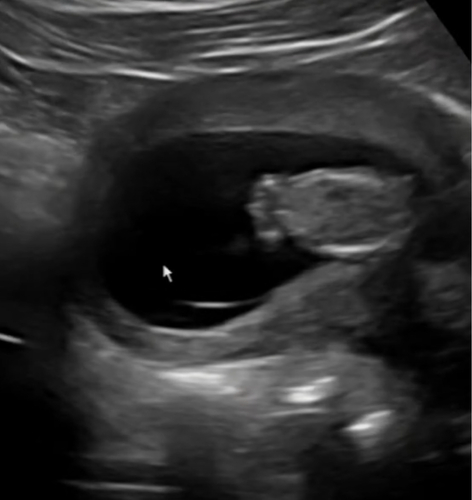

Kunnen jullie hier ook iets uithalen? Dit is namelijk ook vanaf ondergenomen …

2 jaar geleden